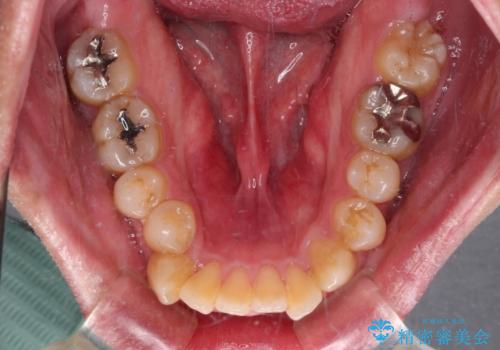

- 口が閉じられないとのことで来院された患者様です。

顎先に力を入れないと唇が閉じきれない口元であったので、上下左右の第一小臼歯4本を抜歯して、ワイヤー装置にて矯正治療を行うこととしました。

2年から2年半の治療期間を想定しており、予定通りの期間で無事に終了することができました。

唇や顎先に力を入れないなくてもスムーズに唇を閉じることができるようになりました。